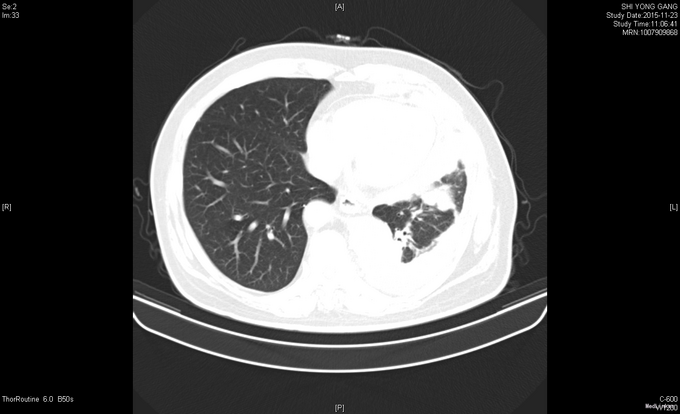

患者于2015年2月中旬无明显诱因出现咳嗽咳痰,中等量白色粘痰,无痰中带血,至当地卫生院予以消炎治疗(具体不详),症状无明显好转。出现胸闷气喘,平卧时加重,无粉红色泡沫痰,无发热,无咯血,至XX医院就诊,查胸部X线提示左侧大量胸腔积液。胸部及上腹部增强CT提示左肺上叶条索灶,左侧胸膜明显不均匀增厚,间皮瘤?转移?左侧胸腔积液,左下肺膨胀不全,肝右叶后段小类圆形稍低密度影,囊肿?胆囊壁增厚。右肾囊肿。腹膜后小淋巴结。2015-03-17 B超引导下行胸膜活检术,术后病理示(左侧胸膜穿刺)镜下见少量异型细胞,免疫组化结果:CK7(++),NapsinA(-),TTF-1(-),CK20(-),Villin(-),Ki-67(<2%+),CK(+),MC(+),结合HE切片、临床表现及影像学资料,符合恶性间皮瘤。头颅MRI未见异常。ECT全身骨显像未见异常。患者拒绝化疗等治疗后出院。后患者症状持续存在,遂于2015-07-21至XX医院就诊,排除禁忌,于2015-07-22予以化疗(培美曲塞二钠1g d1+顺铂40mg d1-3)1周期。并于2015年8月开始间断予以DC+CIK细胞免疫治疗。

查体:左下肺呼吸音低,余查体未见明显异常。 辅查:血常规、血生化等未见明显异常;肿瘤标志物:CA125 846.80IU/ml↑、CA15-3 101.60IU/mL↑、细胞角蛋白19片段(Cyfra21-1)5.25ng/ml↑ 胸部CT示:1、左侧胸膜间皮瘤治疗后,局部心包受侵可能,心包少量积液;2、左肺高密度灶,炎症可能,淋巴管转移待排;3、左侧胸腔少量积液左肺膨胀不全;4、纵隔多发稍增大淋巴结。腹部CT示:1、腹膜后多发稍大淋巴结;2、脾脏肿大;3、右肾多发囊肿;4、左侧胸膜不规则增厚,恶性病变可能,请结合临床;心包少量积液。头颅MRI、骨骼ECT未见明显异常。